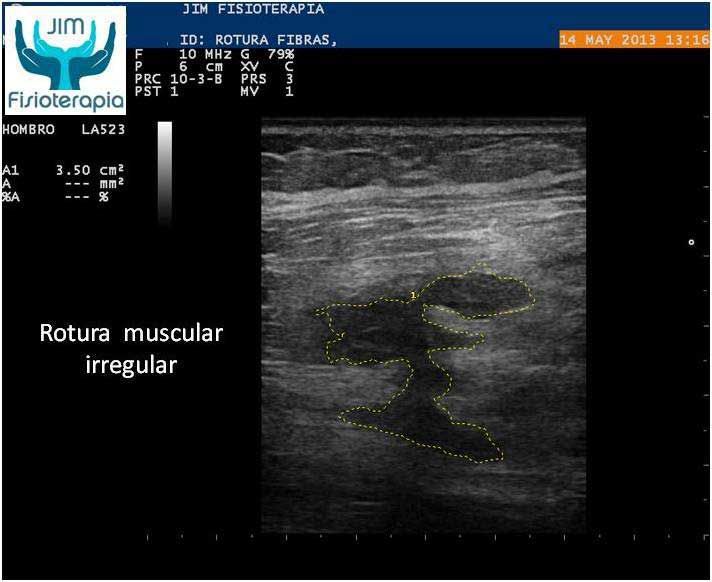

Varón de 47 años, sufre una rotura muscular en el bíceps femoral de la pierna derecha al realizar una brusca contracción excéntrica asociada a movimiento de torsión, al evitar la caída de su motocicleta. Acude a las 72 hrs a nuestra clínica presentando dolor a la palpación, contracción muscular y en la marcha. En la exploración ecográfica se observa una rotura de bordes irregulares.

Se procede a la aplicación de EPI® con el fin de “vaporizar” el derrame producido y favorecer el proceso de regeneración y cicatrización muscular sin fibrosis. En las imágenes se puede apreciar el cambio en el tejido desde la primera sesión, fueron necesarias cuatro sesiones de EPI® hasta lograr la recuperación completa, a partir de la segunda sesión el paciente refirió una desaparición del dolor en la marcha y las actividades cotidianas, complementando su tratamiento con la aplicación de Radiofrecuencia.